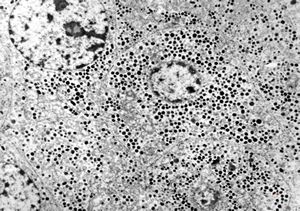

F, 71y. | carcinoid … metastasis to lymphonode